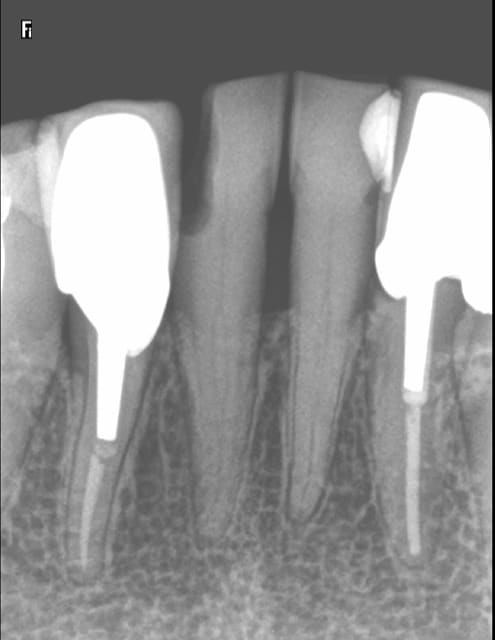

1h pour cette 41 (endo taille empreinte provisoire)

Quicksleeper 5 ostéocentrale en distal. Silence opératoire instantané et le léger engourdissement de la lèvre était dissipé à la fin de la séance.

SX sur entran, largo 3 sur double bague verte pour ouvrir l'entrée.

S1 sur endomaster alterné avec réciproc R 25 ( canal pas perméable du tout au cathétérisme à la lime 10) pour atteindre la LT.

Finition au R25.

Cone scellé au tubuli seal, thermo compaction mac spaden.

Empreinte en mordu.

Note : la 32 date de 2003 à cette époque j'alesais au 50 ca me prenait un peu plus de temps ! -)))))